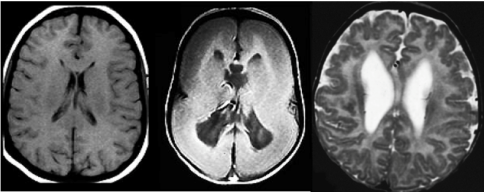

There are two brain formation disorders that are characterized by abnormal folding of the brain before birth: polymicrogyria and lissencephaly. In polymicrogyria, which literally means many (poly-) small (-micro-) folds (-gyria), the surface of the brain develops too many folds and the folds are very small. It can affect just a region of the brain or the whole brain. The symptoms depend on how much of the brain and which particular regions are affected, but some of the common symptoms are epilepsy, difficulty with speaking or chewing and mild to severe intellectual disability.

On the opposite side of the spectrum there is lissencephaly or smooth brain, from the Greek words “lissos” meaning smooth and “enkaphalos” meaning brain. Lissencephaly is a rare disorder characterized by a lack of development of brain folds. Children with lissencephaly generally have severe mental retardation and shortened life expectancy [5,6].

Figure 3. MRI images of a regular brain, a brain with lissencephaly and a brain with polymicrogyria, respectively.